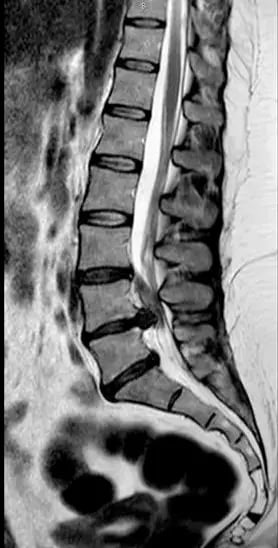

¿Qué es una hernia discal?

Los discos intervertebrales actúan como amortiguadores entre las vértebras. Una hernia discal ocurre cuando parte del disco se desplaza y puede irritar estructuras cercanas, especialmente una raíz nerviosa. Por eso pueden aparecer síntomas como dolor irradiado, hormigueos o pérdida de fuerza.

Hernia discal lumbar: síntomas más frecuentes